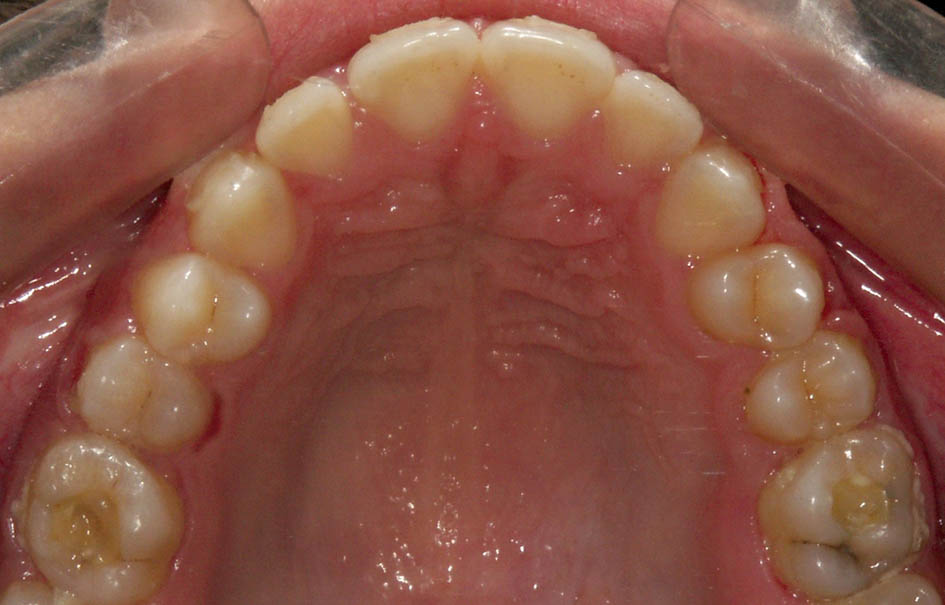

بهترین زمان درمان موقعی است که دندان E لق میشود. اگر یک دندان E باقیمانده، آن را بکشید (شکل 53-5) چون در زمان لق شدن آن همکاری بیمار در استفاده از پلاک فانكشنال کم میشود.

شکل 53-5: قبل از شروع فانكشنال، كشيدن دندان شيري E كه لق شده لازم است. دندانهای 5 در حال رویش هستند.